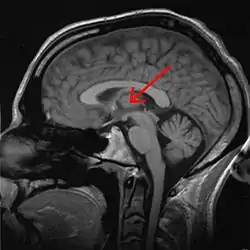

Thalamus

The thalamus (PL: thalami; from Greek θάλαμος, "chamber")[1] is a large mass of gray matter located in the dorsal part of the diencephalon (a division of the forebrain). Nerve fibers project out of the thalamus to the cerebral cortex in all directions, allowing hub-like exchanges of information. It has several functions, such as the relaying of sensory signals, including motor signals to the cerebral cortex[2][3] and the regulation of consciousness, sleep, and alertness.[4]

![]() Thalamus marked (MRI cross-section) | |